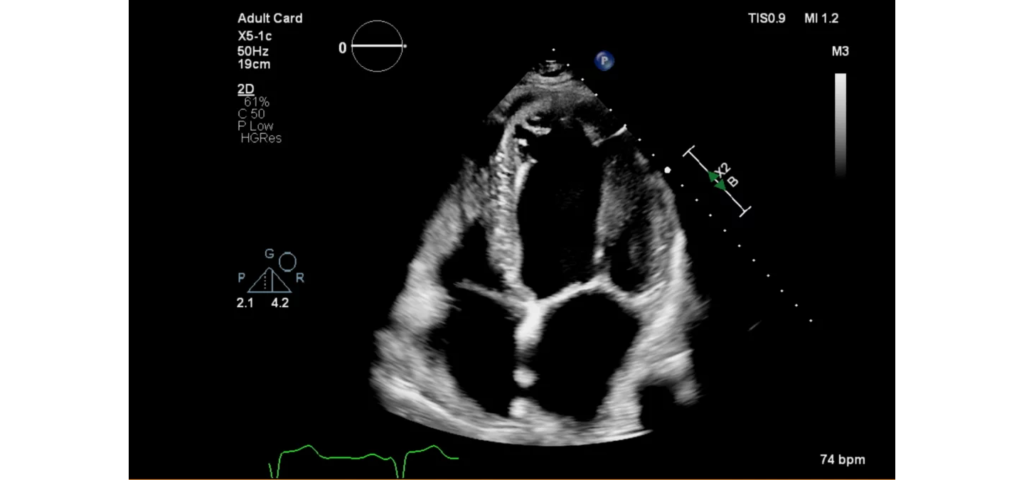

EPIQ CVx, our premium cardiovascular ultrasound system built on our innovative, modular, industry-leading ultrasound platform, has powerful AI-based capabilities and advanced diagnostic solutions to help you transcend today’s complexities and propel echocardiography into the next dimension. This enables you to achieve greater consistency, accessible innovation, smarter workflows, and easier scalability.

Epiq CVx